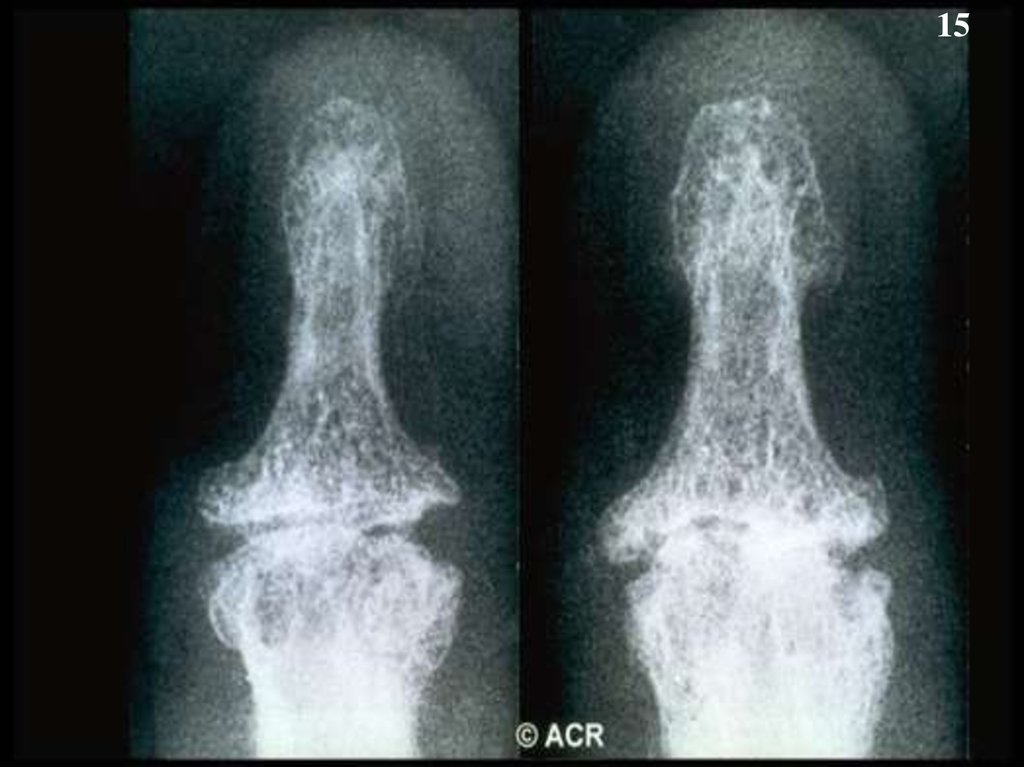

15.

15